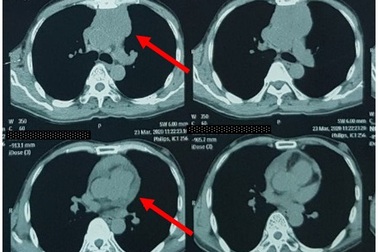

Ung thư tuyến ức - Bệnh lý ung thư hiếm gặpBệnh viện Việt Nam - Thụy Điển Uông Bí (Quảng Ninh) vừa phẫu thuật cắt u tuyến ức cho nam bệnh nhân 68 tuổi, đây là một thể ung thư rất hiếm gặp trong số các bệnh ung thư.